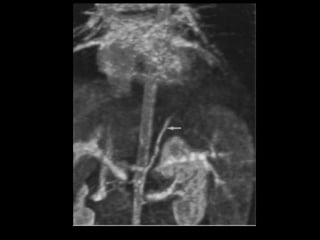

Sequestro pulmonar Definição:segmento de tecido pulmonar que é separado da árvore brônquica e recebe seu suprimento sanguíneo de uma artéria sistêmica; Dois tipos: intralobar e extralobar; A maioria dos sequestros são tipo intralobar; O suprimento vascular em 80-90% dos casos provêm da artéria aorta descendente; Complicações: hemoptise e BCP repetição; Diagnóstico: identificação do vaso anômalo.

Sequestro intralobar cominfecções recorrentes